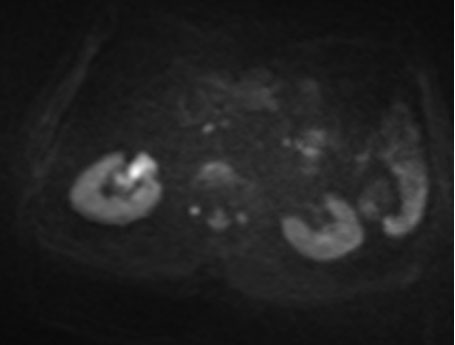

Renal magnetic resonance imaging (MRI) was performed for better characterization of the mass and showed a 3.8×2.2×3.2 cm exogenous lower pole right renal lesion with multiple thickened septations, and a soft tissue component showing heterogeneous signal on T2 images suggestive of RCC. An additional right renal pelvic mass measuring up to 2 cm in the transverse axis was found, neoplastic in nature, suggestive of TCC (Figure 1, Figure 2, Figure 3).

Figure 2: Diffusion-weighted image showing right renal pelvis TCC.